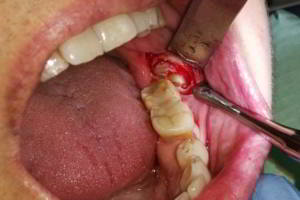

· Imagen 2, leer más...

La extirpación de la cápsula de un quiste recibe el nombre de quistectomía. Dicha intervención varía en función del tipo, localización y tamaño del mismo. Algunos pueden aparecer aislados (residuales), otros relacionados con algún diente erupcionado (radicular, periodontal lateral), con dientes no erupcionados (foliculares, paradentales) y algunos pueden ser unilobulados o bien multilobulados (botrioide). De cualquier forma, el tratamiento por lo general debe ser su extirpación completa.